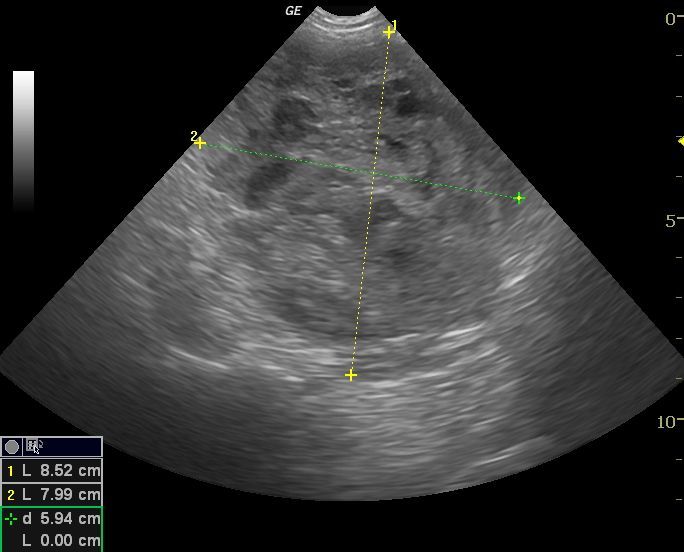

La ecografía es uno de los medios de diagnóstico que más ha evolucionado en los últimos años. Es un método no invasivo, inocuo y que permite dar gran información en muchos campos de la medicina interna, reproducción, oftalmología, y muy especialmente en cardiología.

La Ecografía permite una exploración completa de los distintos órganos aportando datos objetivos para conseguir un diagnóstico preciso , establecer un tratamiento adecuado y realizar un seguimiento de cada caso.

La ecocardiografía es una herramienta imprescindible en el diagnóstico y seguimiento de las patologías cardíacas, tanto congénitas como adquiridas, ya que nos permite visualizar el interior de corazón, pudiendo observar sus paredes, sus válvulas y aportando datos objetivos sobre la funcionalidad cardíaca. Además la ecocardiografía Doppler, (Doppler espectral, pulsado y continuo, y Doppler de flujo color) permite la evaluación de la dirección y la velocidad del flujo sanguíneo a traves del corazón y de los grandes vasos.